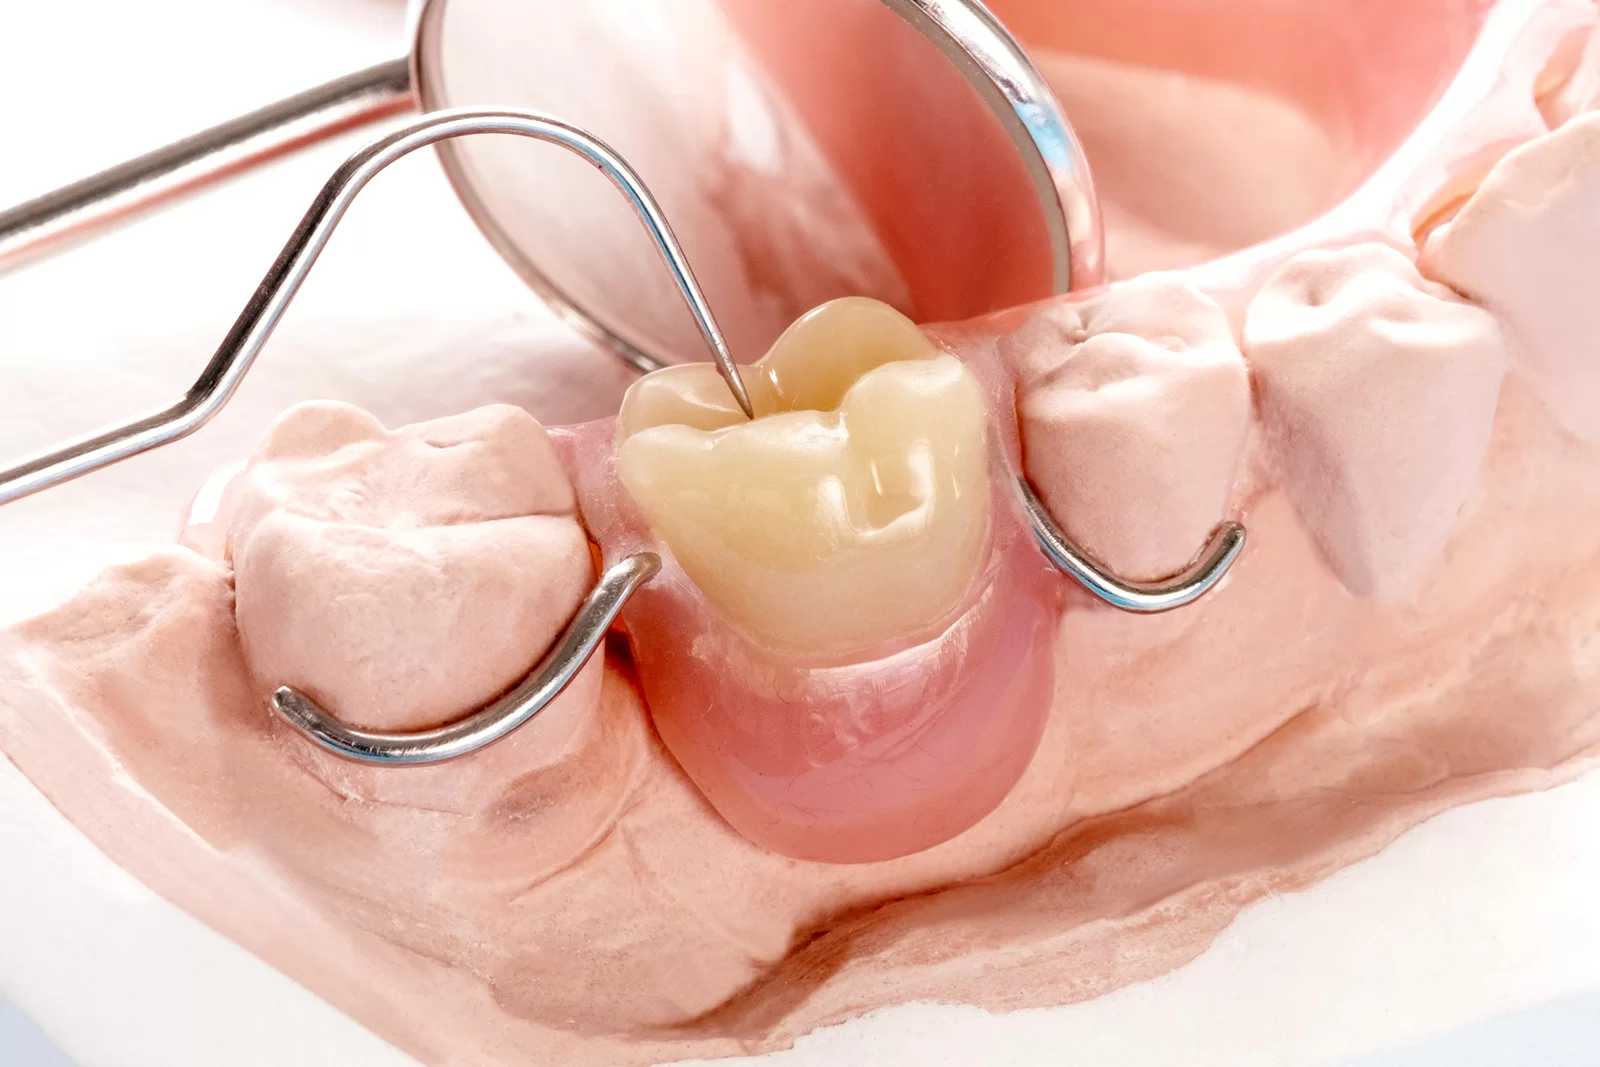

ブリッジ治療は、失った歯を補う方法として多くの方に選ばれている治療法です。ブリッジ治療では、失われた歯の両側にある健康な歯を支えにして、その間に人工の歯を設置します。しかし、この治療にはいくつかの欠点もあります。ここでは、その具体的な欠点について詳しく見ていきましょう。